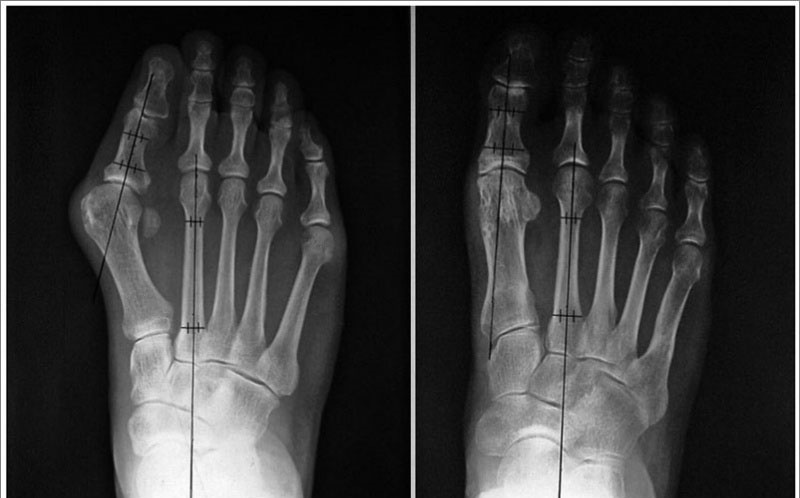

- рентгенография стоп в 3-х проекциях - в целях определения степени деформации стопы, а также выявления сопутствующих патологий;